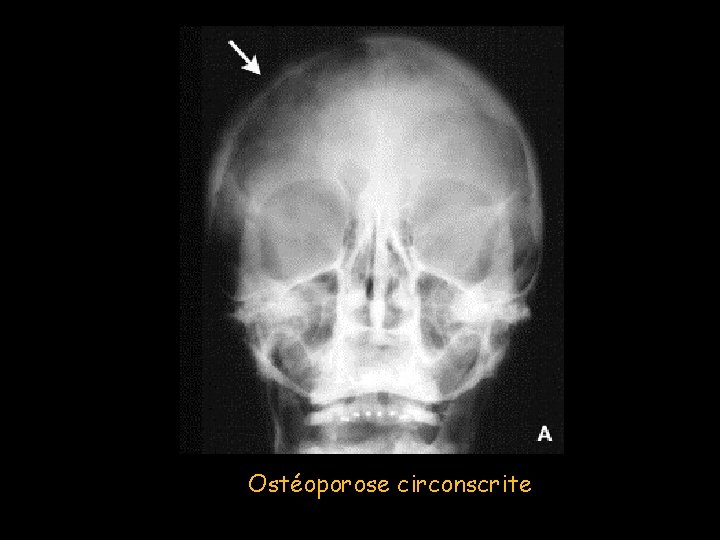

Maladie de Paget • Ostéite déformante de cause inconnue avec remodelage excessif anarchique des pièces squelettiques • 10 % de la population après 85 ans, • Prédominance masculine • Généralement asymptomatique, intéresse: – Crâne : 25 à 65 % des cas – Classique ostéoporose circonscrite de Schuller + remodelages osseux à type d’hypertrophie des pièces osseuses et de dédifférenciation cortico-médullaire

Ostéoporose circonscrite